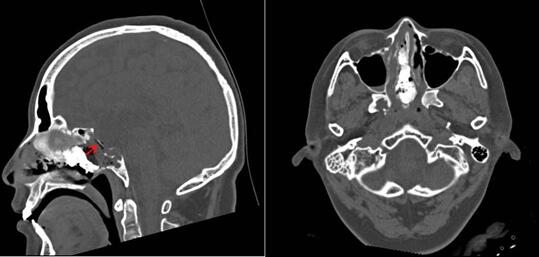

术后CT可见鞍底骨性重建(红箭头所示)

任铭主任介绍:常用的脑脊液鼻漏修补是用肌肉、筋膜、脂肪等自体组织或医用合成修复材料等铺盖漏口,实施压迫,或用生物胶粘合,这种修补方法虽然也是多层修补,但是并不十分牢固,因为所有的修补材料都是离体状态的,离体的组织缺乏血运,可以出现修复材料生长不良甚至坏死。本例患者在手术中采用新的“三明治”封堵法,在显露右侧蝶窦开口后,首先制作带蒂右侧鼻中隔粘膜瓣,翻转后置鼻咽部备用,然后磨除蝶骨嘴及蝶窦腹侧壁进入窦腔,去除窦内瘢痕组织及前次手术填塞物,充分暴露鞍底骨质缺损区,去除周边粘膜及纤维增生组织露出光滑的骨面,镜下探查术区,仔细寻找漏口,确认唯一漏口后覆盖可吸收人工硬膜,取鼻中隔骨片嵌入破损区行颅底重建,最后将备好的带蒂右侧鼻中隔粘膜瓣广泛贴覆于鞍底骨质表面,生物胶封固。整个封堵过程需要用三层材料,一层一层覆盖压迫,所以形象的称为“三明治”封堵法。手术共用时1个小时顺利结束。任铭主任强调,这种方法修补鼻漏牢固安全,可以实现“一劳永逸”,重建的组织一个月后就能全部长好,三个月后患者可以乘坐飞机。

任铭主任介绍,像王女士这样的情况,脑脊液鼻漏合并颅内感染,一定要先堵漏,再消炎,同时给予腰大池引流,将炎性脑脊液都引流出来,患者就会渐渐康复。脑脊液鼻漏是脑脊液通过颅底或其他部位骨质缺损处流出,经过鼻腔,最终流出体外。原因多为创伤引起,可在数天、数周或数年后出现,主要表现为鼻腔间断或持续流出清亮、水样液体。保守治疗时要卧床休息,半坐位,防止感冒,保持大便通畅,不要行屏气、擤鼻及咳嗽等增加颅内压动作;保持鼻腔局部清洁及脑脊液流出畅通,避免局部堵塞导致脑脊液逆流,同时应用抗生素,对于保守治疗无效者,应积极采取手术治疗封堵漏口。目前成熟的漏口修补方法为神经内镜下“三明治”修补法,关键修补层次为三层:硬膜下嵌入漏口层、硬膜外贴覆层,和带蒂粘膜瓣骨面贴覆层,尤其最后一层粘膜瓣贴覆层由于是带血运的组织,因而愈合能力大大提高。本例患者由于5年后出现鼻漏,考虑与前次手术鞍底骨质缺损,缺乏骨性支撑有关,因而我们取鼻中隔的薄骨片为患者同时进行了颅底骨性重建。(李亚静)